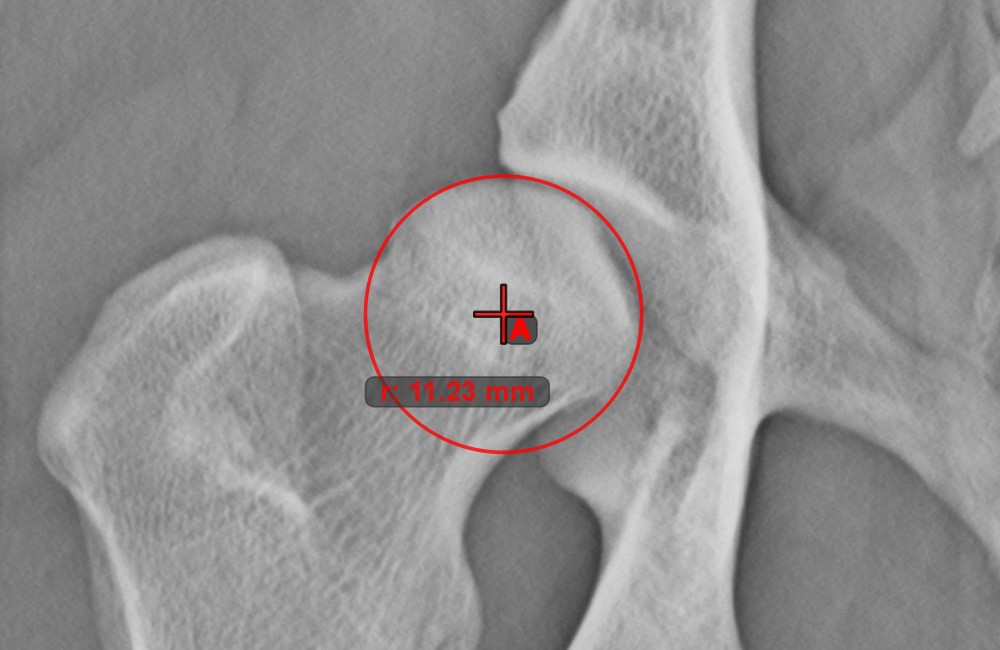

Kreis mit definiertem Radius¶

Zeichnen Sie einen Kreis mit festem Radius mit dem Werkzeug Kreis mit definiertem Radius

. Später kann nur die Position des Kreises in der Szene geändert werden.

Wählen Sie das Werkzeug aus der linken Symbolleiste aus und weisen Sie es einer der verfügbaren Maustasten zu. Setzen Sie den Ursprung des neuen Kreises in der Szene oder wählen Sie einen bereits vorhandenen Punkt aus. Geben Sie den gewünschten Radius des Kreises an und drücken Sie OK

, um die Messung abzuschließen.